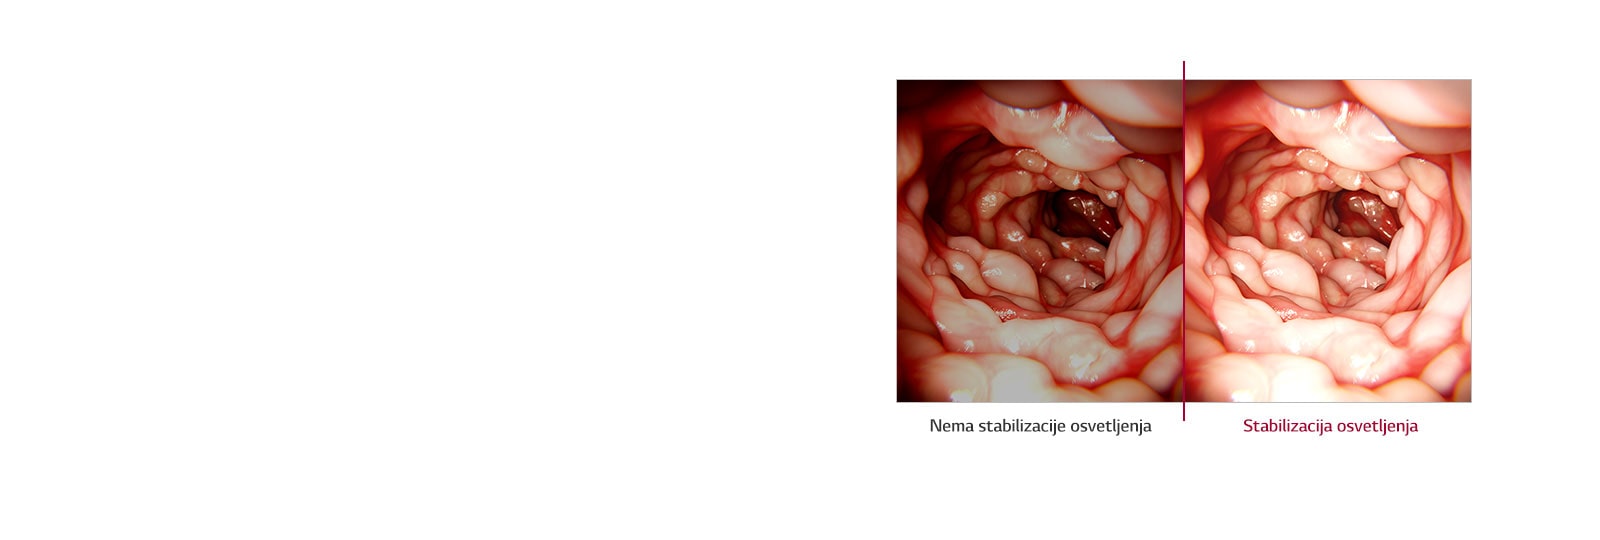

Stabilizacija osvetljenja

Da